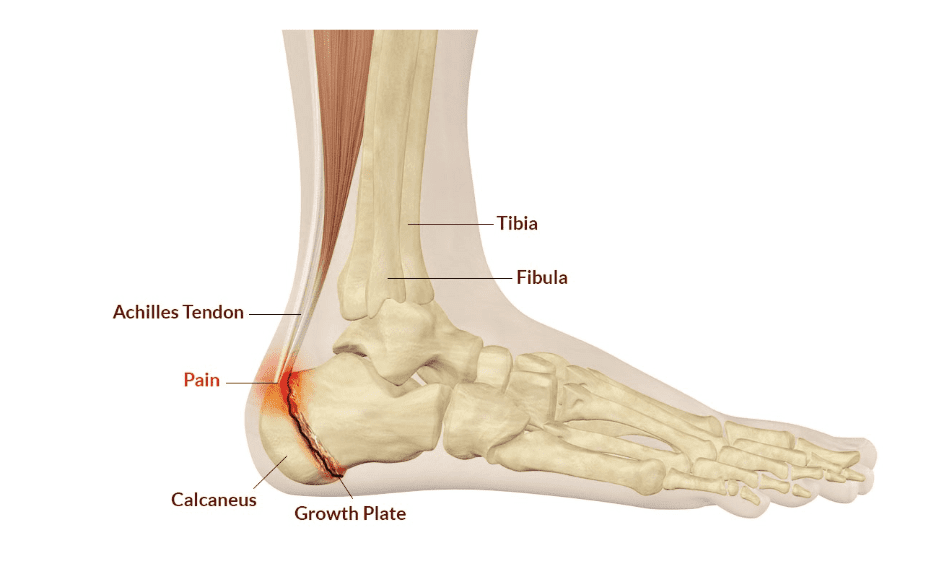

The condition arises from inflammation of the growth plate at the heel (calcaneus), caused by the natural growth imbalance between the growing bones and the surrounding soft tissues. The Achilles tendon, which attaches to the heel, may pull on the growth plate during periods of rapid growth, causing irritation or micro-tears.

- Rapid growth during puberty, which leads to a mismatch between the growth of the heel bone (calcaneus) and surrounding soft tissues, placing strain on the Achilles tendon and the growth plate at the heel.

Sever’s Disease is typically diagnosed through a thorough clinical evaluation. Dr Shikha Parmar will assess the child’s history of heel pain, activity levels, and any potential triggers. A physical examination will be performed to check for swelling, tenderness, and pain around the heel and Achilles tendon.

Imaging, such as X-rays, may be used to rule out other causes of heel pain, such as fractures or infections. X-rays can help confirm the presence of inflammation in the growth plate or to check for other structural issues.

Low Level Laser Therapy (LLLT), also known as Photobiomodulation Therapy (PBMT), is a gentle, evidence-based treatment that targets the underlying cause of Sever’s Disease: inflammation at the Achilles tendon insertion, growth-related traction stress, and local immune imbalance at the heel growth plate. It promotes healing without mechanical stress to the developing calcaneal structures.